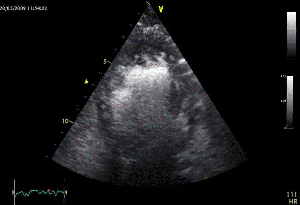

Όταν, λοιπόν, αποφασίζουμε να προχωρήσουμε, το αποτέλεσμα πρέπει να είναι κάπως έτσι:

Και στις MPR τομές, να μη φαίνεται σκιαγράφηση του σώματος του ωτίου — ακόμα και ένα μικρό peri-device leak (PDL) θα τo «ασπρίσει» –, ούτε βέβαια θρόμβος (device-related thrombosis, DRT).